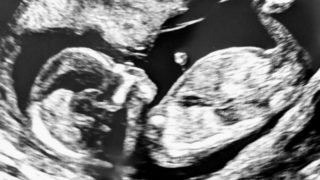

育児 妊婦検診 私は今お腹に3人目の赤ちゃんがいて、もう25週目(6ヶ月)になりました。去年、次男が入園してやっと自分のための時間が少しできて、社会へ復帰の夢をみていたけど…また一から始まるのです~妊娠初期のつわりが酷かった時期にはちょうどスコットランドの... 2021.05.08 育児